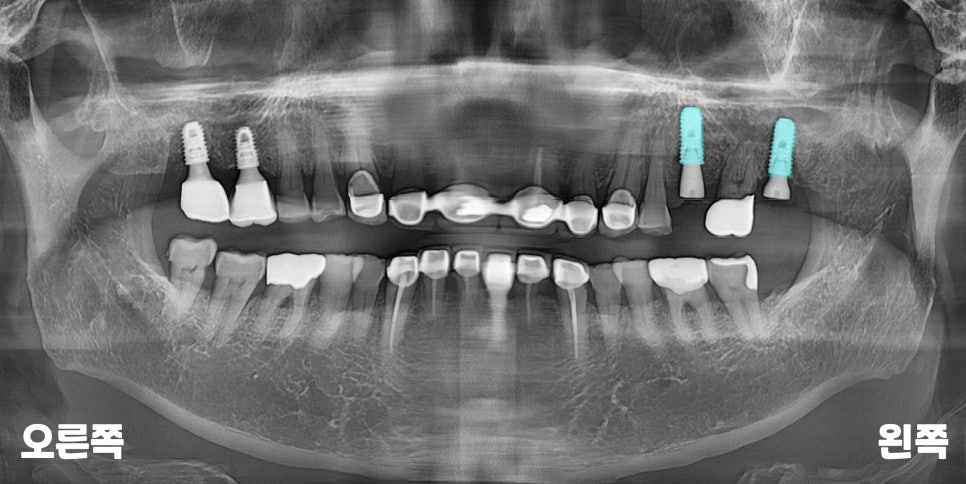

꼼꼼한 데이터를 중심으로

건강하게 식립된

서울바르디치과의 임플란트

모습입니다.

단단한 고정을 위해

부족한 뼈는 이식재로

보강해 주고,

상악동 거상술을 통해

주변의 구조물이

다치지 않도록 했습니다.

시간이 지날수록

임플란트 주변으로

푸석하던 턱뼈가

점차 단단한 흰색으로

변하고 있습니다.

채워두었던 뼈이식재도

본래의 치조골로

잘 자리를 잡고 있고,

뿌리 끝 주변의

얇은 상악동 막도

깨끗하게 잘 유지되는

모습이네요.^^